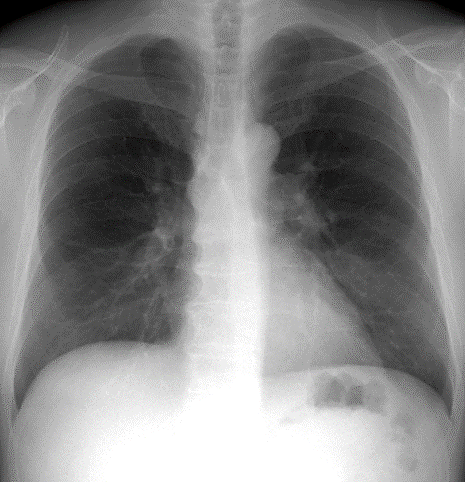

胸部X線検査

X線撮影検査の項目をご参照ください。

低被ばく肺CT検査のご案内

2024年のがん死亡数1位は肺がんで約7万5千人を超えています

低線量CTとは?

通常のCTよりも被ばく線量を1/7に減らしながら、胸部X線画像では見逃されやすい早期の小さな肺がんや肺の異常を発見できる検査です。検査時間は5分程度です。